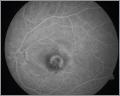

trockene AMD

feuchte AMD